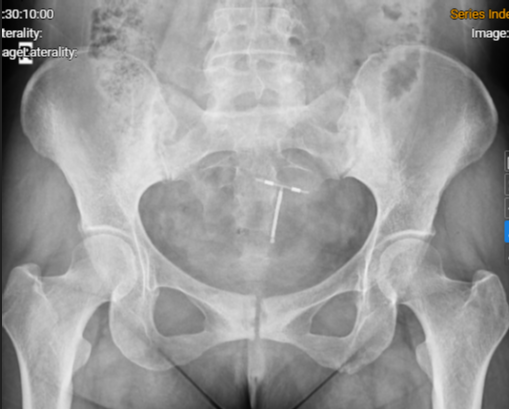

Hình ảnh phim chụp Xquang khớp cùng chậu của người bệnh: Viêm khớp cùng chậu độ III - Ảnh BSCC

Người bệnh được chỉ định chụp cộng hưởng từ (MRI) cột sống lưng, cột sống ngực và khớp cùng chậu, xét nghiệm cho thấy người bệnh mang kháng nguyên HLA-B27 dương tính. Người bệnh được chẩn đoán: Viêm cột sống dính khớp, một bệnh tự miễn mạn tính thuộc nhóm bệnh lý cột sống – khớp có thể gây biến dạng, dính khớp, tàn phế nặng nếu không được điều trị kịp thời và đúng cách.